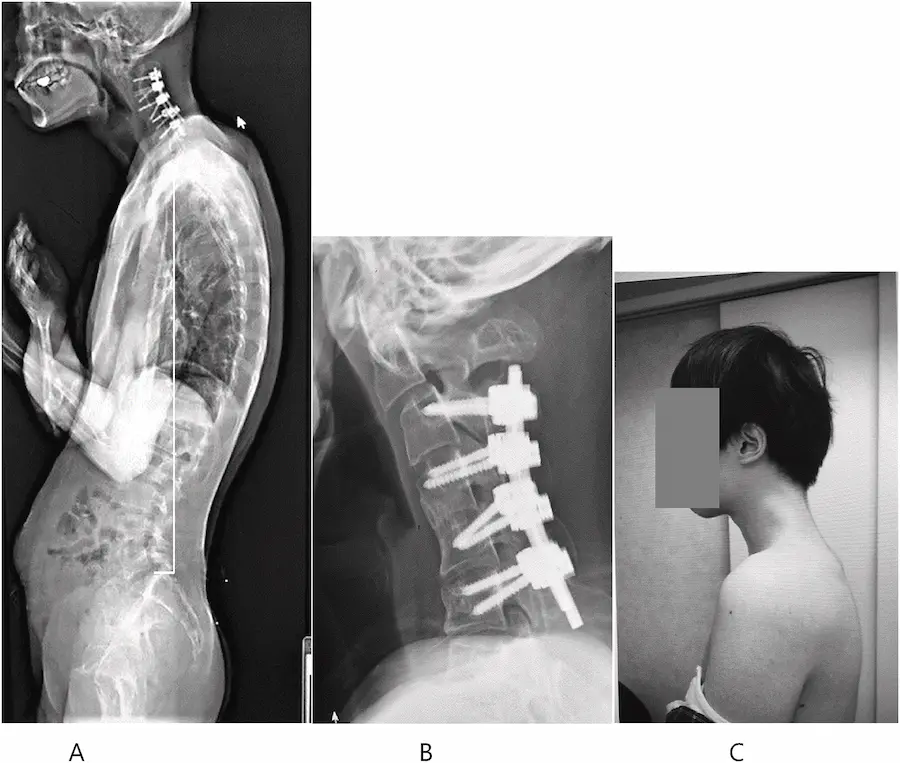

起初嘗試以護頸裝置改善情況,但因患者出現麻木感及不適,最終決定採行外科手術治療,切除受損椎骨及疤痕組織,再以金屬固定裝置強化頸椎結構,術後追蹤顯示,經歷半年復健,患者已能將頭部維持於正常水平,一年內無復發,抬頭與吞嚥功能也大幅改善。